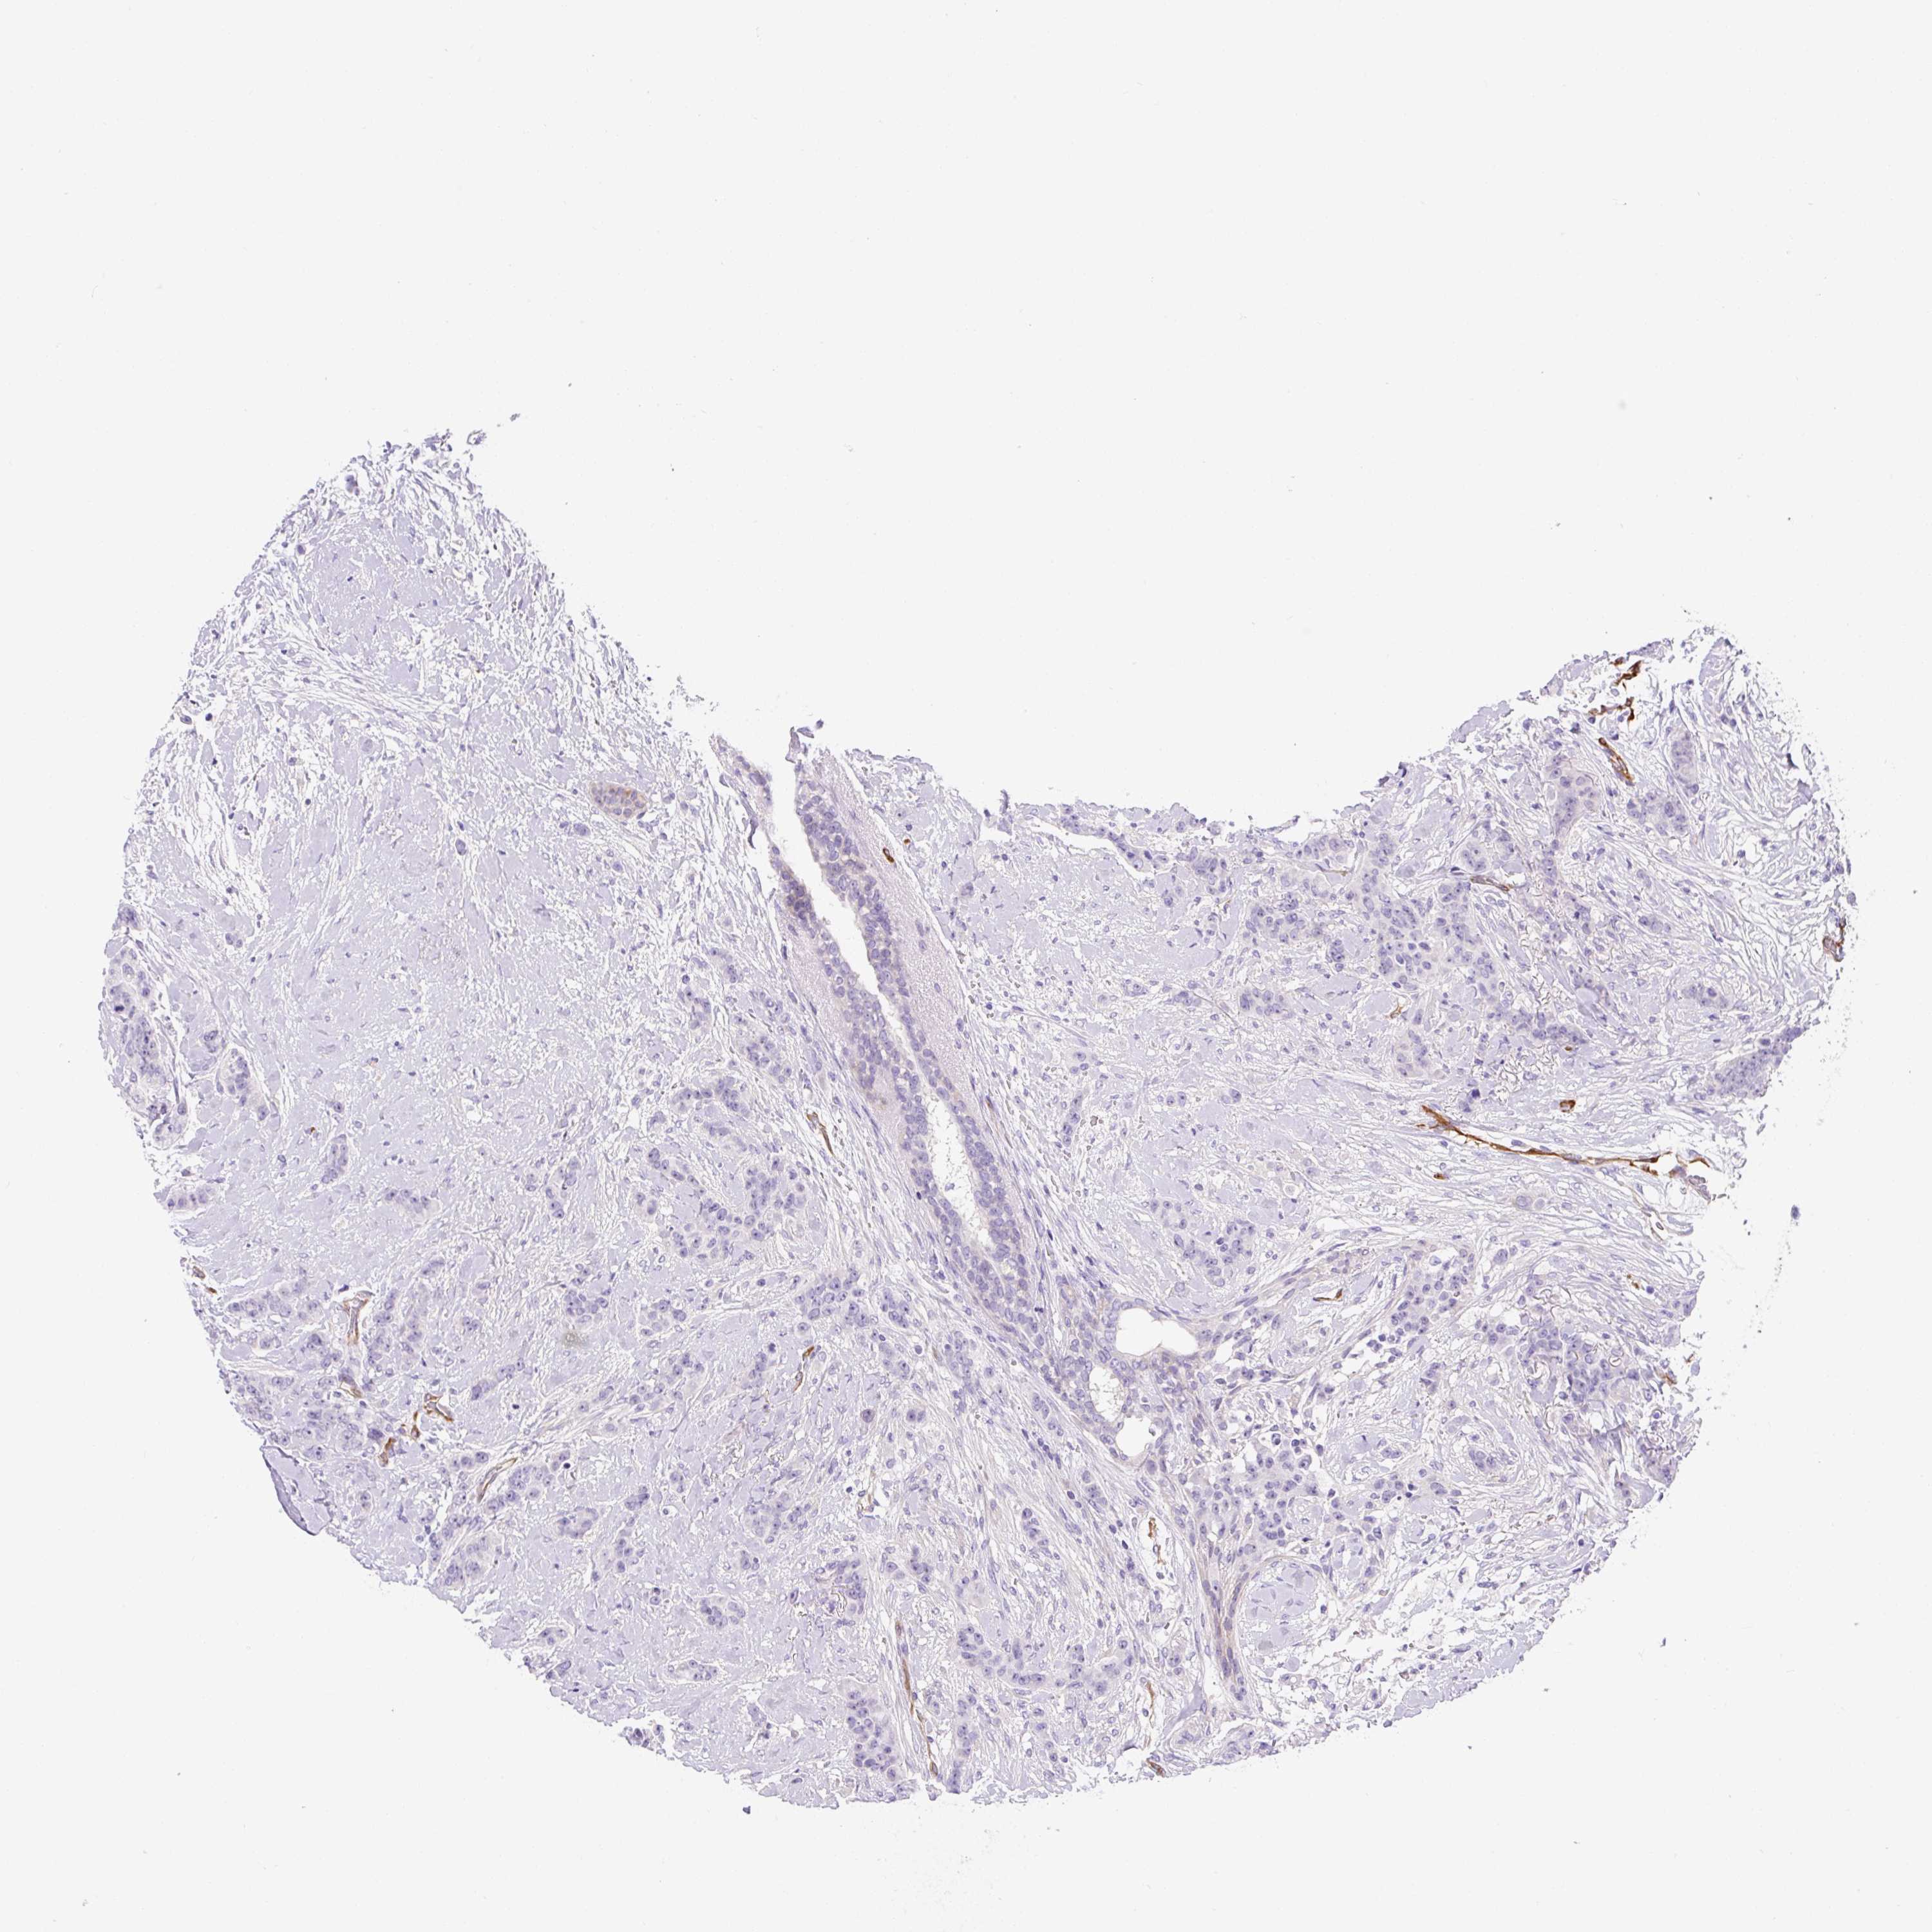

BRCA TCGA BRCA VALIDATION PROTEIN EXPRESSION

ANTIBODIES

AND

VALIDATION